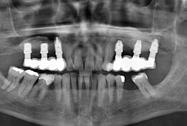

Figura 4. Aspecto de los pilares después de la aplicación de la radiofrecuencia. Arco dentario superior e inferior.

se usó pilar atornillado Straumann (Figura 4).

Estudios radiográficos de inicio

En la radiografía panorámica (Figura 5) se observan en 20 dientes los brakets viejos, en los molares 16, 27 las bandas, el canino 13 retenido en el paladar, el botón de Nance, la